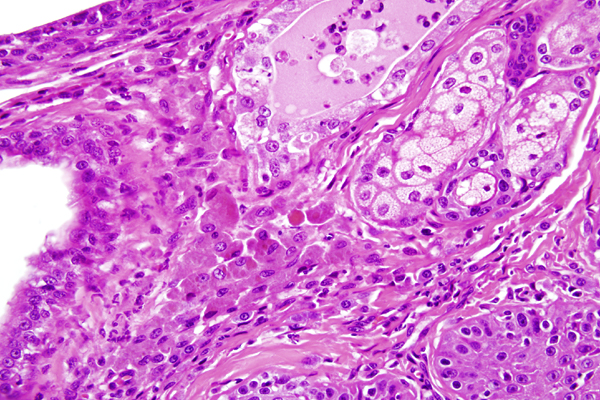

The stroma contains multifocal aggregates of many lymphocytes, fewer plasma cells, neutrophils and macrophages that are often laden with brown material (secretory product)(arrows).

The stroma contains multifocal aggregates of many lymphocytes, fewer plasma cells, neutrophils and macrophages that are often laden with brown material (secretory product)(arrows).